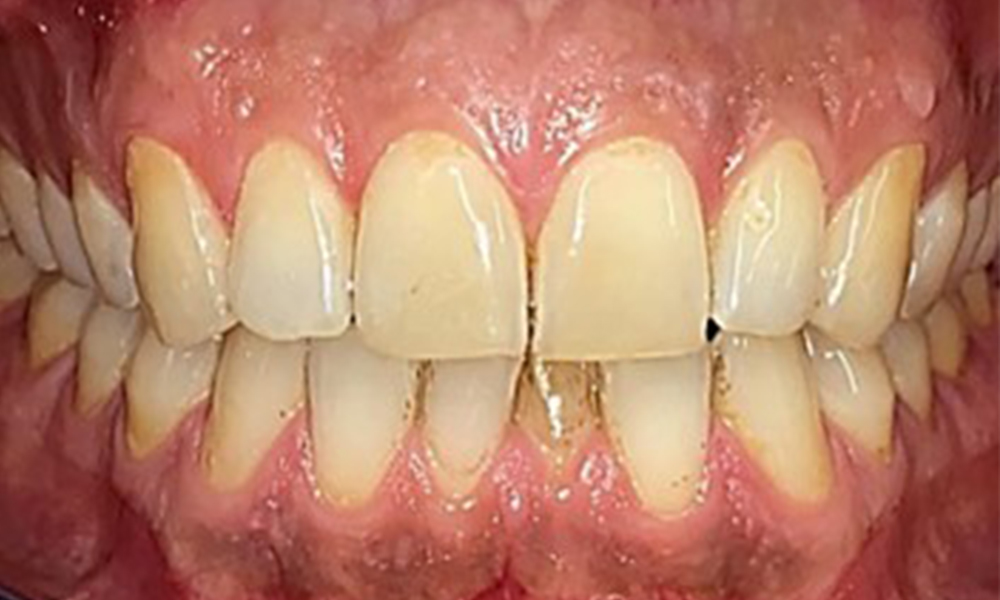

Extra- und Intraoraler Befund

Extraoral sind keine pathologischen Befunde festzustellen, intraoral zeigen sich bei der Frontalansicht im Bereich der keratinisierten Gingiva und am Übergang zur beweglichen Schleimhaut bräunlicheVerfärbungen (Abb. 2), welche auf den Nikotingenuss zurückzuführen sind. Am Gaumenbereich zeigen sich insbesondere im Bereich Oberkiefermolaren palatinal weißliche Schleimhautveränderungen, die ein Hinweis auf einen erhöhten Verhornungsgrad sind und ebenso auf den Nikotingenuss zurückzuführen sind. Die Zunge ist mit einem weiß-bräunlichen abwischbaren Belag versehen.